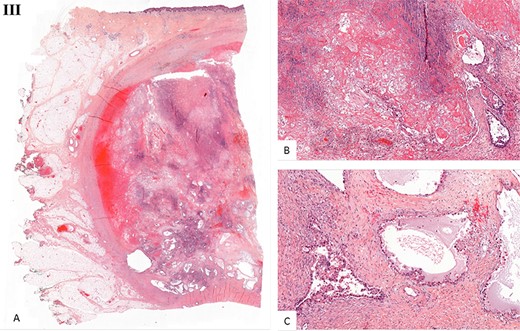

Histological examination. (I) Microscopic examination of the biopsy: A. Glandular and focal papillar pattern , HE stain x200 B. Hobnail morphology of tumoral cells, HE stain x400 C. Nests of neoplastic clear cells, HE stain x400 D. Nuclear immunoreactivity with anti-PAX8 antibody, x200 E. Nuclear immunoreactivity with anti-HNF-1β antibody, x200 F. Wild type pattern with anti-p53 antibody, x200. (II) Surgical specimen. Resection of the parietal mass with free margins after radiotherapy. (III) Microscopic examination of resected specimen: A. Nodular lesion involving dermis and hypodermis, HE x5 B. Hemorrhage, fibrotic and necrotic changes, HE x50 C. Microcystic predominant pattern, HE x100.

Gross histopathological examination revealed a nodular lesion involving the dermis and hypodermis, measuring 7 × 5 cm, with necrotic, hemorrhagic and fibrotic changes. Microscopic examination of the resected specimen showed a similar histopathology to the biopsy (Fig. 3III).